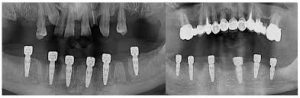

اگر مشکوک هستید که ایمپلنت در موقعیت نامناسبی قرار گرفته است، بهترین کار انجام عکسبرداری سه بعدی با اشعه ایکس (CBCT) برای ارزیابی موقعیت دقیق ایمپلنت و سلامت استخوان اطراف آن است.

- ارزیابی وضعیت بافت های استخوانی به صورت بصری و با اشعه ایکس.